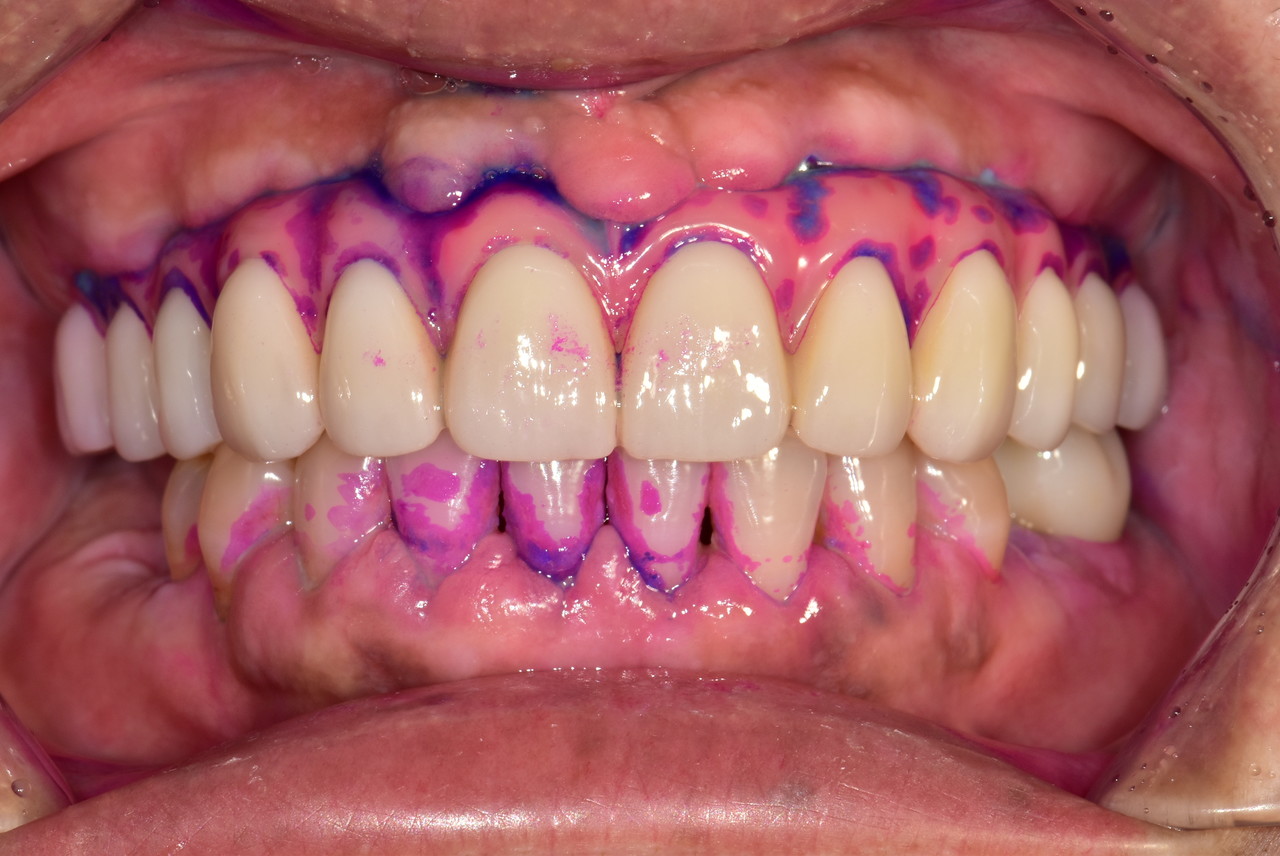

치면착색검사

매일 칫솔질을 해도, 세균은 남아있습니다

입 속 유해균은 풍치와 충치의 주범이며,

잇몸 혈관을 통해 당뇨, 치매, 폐렴 등 전신질환으로 번질 수 있습니다.

입안사진